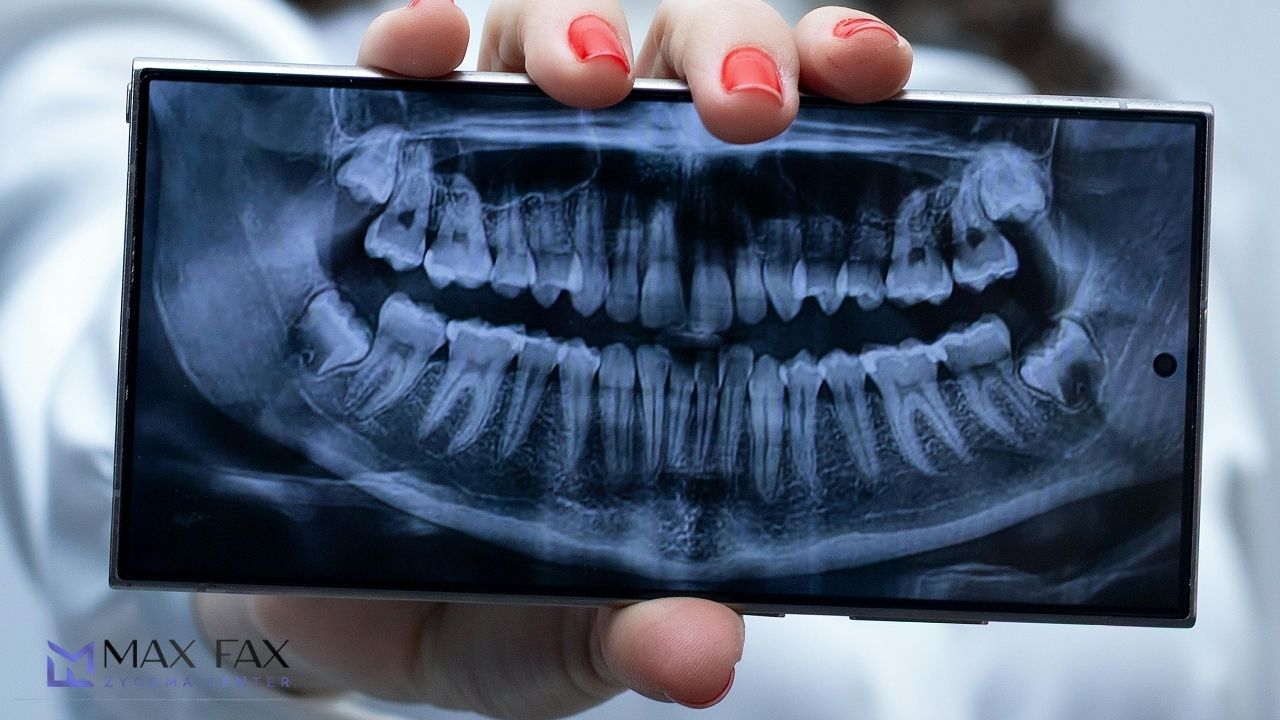

During consultation, it is determined whether the patient is suitable for the procedure. Clinical and radiological examinations are performed, typically including volumetric tomography and panoramic X-rays. The zygomatic arch region is evaluated in detail.

These images allow the surgeon to plan the exact implant placement angle and position with precision, according to the anatomy of the cheekbone as part of the Zygomatic Implant Steps.